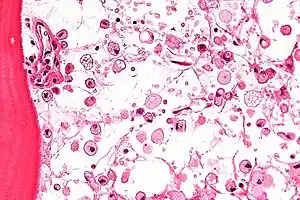

The disease is caused by a defect in housekeeping gene for lysosomal glucocerebrosidase (also known as beta-glucosidase, EC 3.2.1.45, PDB: 1OGS) on the first chromosome (1q22). The enzyme is a 55.6-kilodalton, 497-amino acid-long protein that catalyses the breakdown of glucocerebroside, a cell membrane constituent of red and white blood cells. In Gaucher disease, the enzyme is unable to function correctly and glucocerebroside accumulates. The macrophages that clear these cells are unable to eliminate the waste product, which accumulates in fibrils, and turn into 'Gaucher cells', which appear on light microscopy to resemble crumpled-up paper.[5]

A diagnosis can also be implied by biochemical abnormalities such as high alkaline phosphatase, angiotensin-converting enzyme, and immunoglobulin levels, or by cell analysis showing "crinkled paper" cytoplasm and glycolipid-laden macrophages.